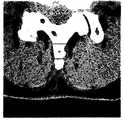

表1は、3番目の棘突起下部の傾きを測定した表である。脊椎狭窄症患者103名を対象として脊椎部分を軸方向に10枚ずつCT(Computer Tomography)撮影し、その中から、棘突起部分が撮影された映像を用いて傾きを算出した。 Table 1 is a table in which the inclination of the lower part of the third spinous process was measured. CT (Computer Tomography) images of 10 spine portions in the axial direction were taken for 103 patients with spinal stenosis, and the tilt was calculated from the images of the spinous process portions.

表2は、4番目の棘突起下部の傾きを測定した表である。脊椎狭窄症患者103名を対象として脊椎部分を軸方向に10枚ずつCT撮影し、特に棘突起部分が撮影された映像を利用して傾きを算出した。 Table 2 is a table in which the inclination of the lower part of the fourth spinous process was measured. CT images of 10 spine portions in the axial direction were obtained for 103 patients with spinal stenosis, and the inclination was calculated using an image in which especially the spinous process portions were taken.